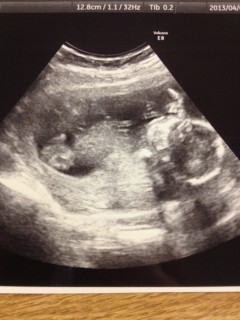

高齢ですが、何とか今のところ元気な、赤ちゃん。足が2日ぶん長いみたい。本日性別が、分かり、女の子だそうです。

先月より大きくなっていて感動! そしてエコーで見ていると股間にチラッ…! あった!(笑)

先生も、男の子だね~♪とのことで、待望のやんちゃ坊主でした☆ エコーで見ている間中ずっと動き回って、元気な子でした☆ これから服など買い揃えたいと思います♪♪

大きさはおっきめみたいです!

三週間ぶりの検診での写真(>_<)まだ性別はわかりませんが無事元気に成長してます♪ただ食生活が不規則なのを注意されちゃいました。こんなに可愛いベビたんの為にもっと色々努力しなきゃと改めて思いました(>_<)